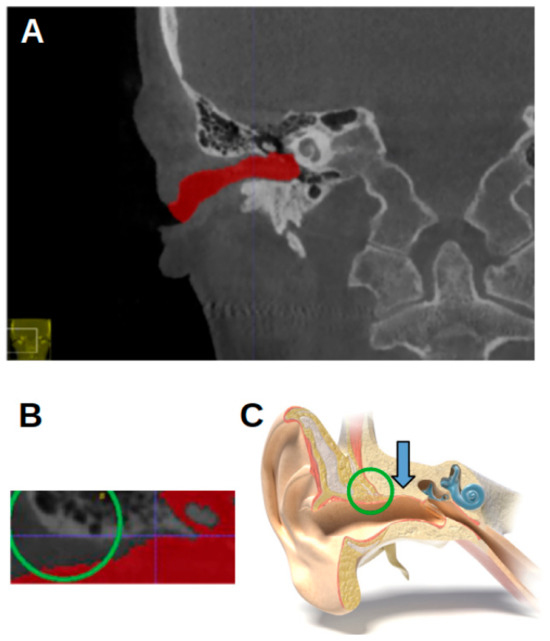

Figure 3 shows the ITK-SNAP window with segmentation, with the axial view shown in the upper-left image. In the first four landmarks, the crosshairs were placed such that they fell inside the segmentation of the acoustic meatus.

Figure 3. ITK-SNAP window. (A) Axial view. (B) Sagittal view. (C) Three-dimensional rendering of acoustic meatus. (D) Coronal view.